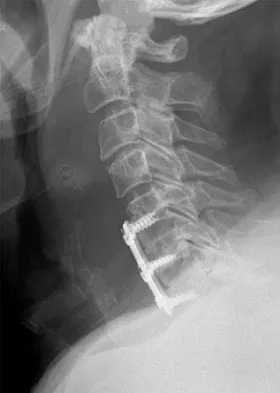

A 45-year-old man undergoes an anterior cervical diskectomy and fusion at C5-6 and C6-7 with instrumentation. During the first postoperative visit at 1 week, the patient reports difficulty swallowing and mild anterior cervical tightness. The anterior wound is benign and the patient denies any dyspnea or shortness of breath. A postoperative radiograph is seen in Figure 25. What is the most appropriate management at this time?

Explanation

The radiograph shows significant prevertebral soft-tissue swelling following a two-level anterior cervical diskectomy and fusion. The incidence of dysphagia 2 years after anterior cervical spine surgery is 13.6%. Risk factors for long-term dysphagia after anterior cervical spine surgery include gender, revision surgeries, and multilevel surgeries. The use of instrumentation, higher levels, or corpectomy versus diskectomy did not significantly increase the prevalence of dysphagia. Lee and associates demonstrated that while dysphagia after anterior cervical spine surgery is a common early finding, it generally decreases significantly by 6 months with nonsurgical management. A minority of patients experience moderate or severe symptoms by 6 months after the procedure. Female gender and multiple surgical levels have been identified as risk factors for the development of postoperative dysphagia. Lee MJ, Bazaz R, Furey CG, et al: Risk factors for dysphagia after anterior cervical spine surgery: A two-year prospective cohort study. Spine J 2007;7:141-147.